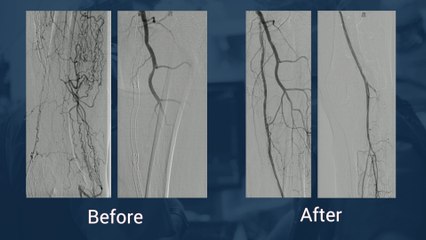

Occlusion chronique coronaire - Exemple 2

Désobstruction d'une occlusion chronique coronaire.